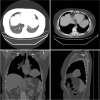

Patients concerns: We recently encountered this type of FLAC in a 51-year-old female patient. A computed tomography (CT) scan of the chest revealed a 74 × 51-mm sized tumor in the lingual segment of the superior lobe of the left lung. Among the tumor markers, serum AFP was elevated (816.2 ng/mL).